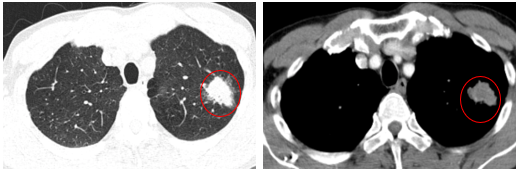

-         Chụp cắt lớp vi tính lồng ngực (06/2025): Nhu mô đỉnh phổi trái có khối tổ chức kích thước ~35x25mm, bờ không đều, có cắt cụt một số nhánh phân thùy đỉnh, ngấm thuốc mạnh không đồng nhất sau tiêm. Thuỳ trên và dưới có nốt đặc nhỏ đường kính 2mm.

Hình 1: Nhu mô đỉnh phổi trái có khối tổ chức kích thước ~35x25mm, bờ không đều, có cắt cụt một số nhánh phân thùy đỉnh, ngấm thuốc mạnh không đồng nhất sau tiêm